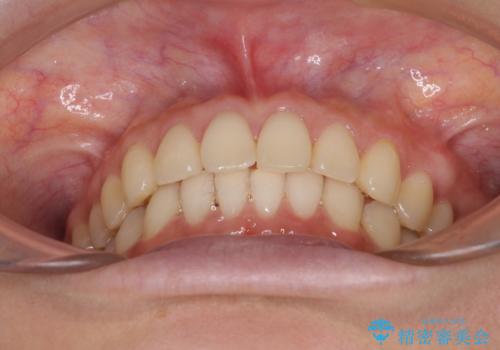

インビザラインによるディープバイトの改善

インビザラインによる上下歯列の遠心移動(後方移動)と、それに伴う近心傾斜(前方傾斜)の改善により、口元の突出感とディープバイトを改善することとしました。

咬合状態が大きく変化したため、治療後半では咬み合わせの位置が定まらなくなりました。上下の前歯に後戻り防止用のワイヤーを装着し、奥歯の咬合をフリーにしたことで1ヶ月ほどで咬み合わせが定まりました。